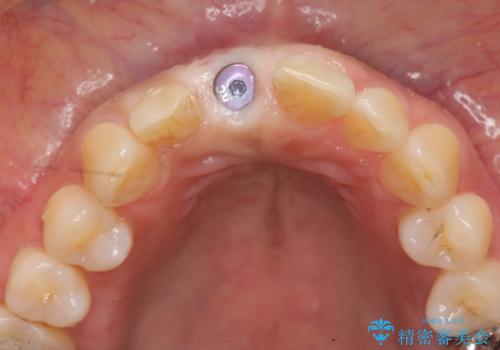

骨造成を伴う前歯のインプラント治療

審美的・機能的に良好な位置に埋入するには、骨量が十分ではなかったため骨の造成を併用したインプラント埋入外科手術を行います。

前歯のインプラントを審美的に仕上げるには、インプラント周囲に十分な骨の量と厚みのある歯肉、そして埋入位置の精密な位置付けが重要です。